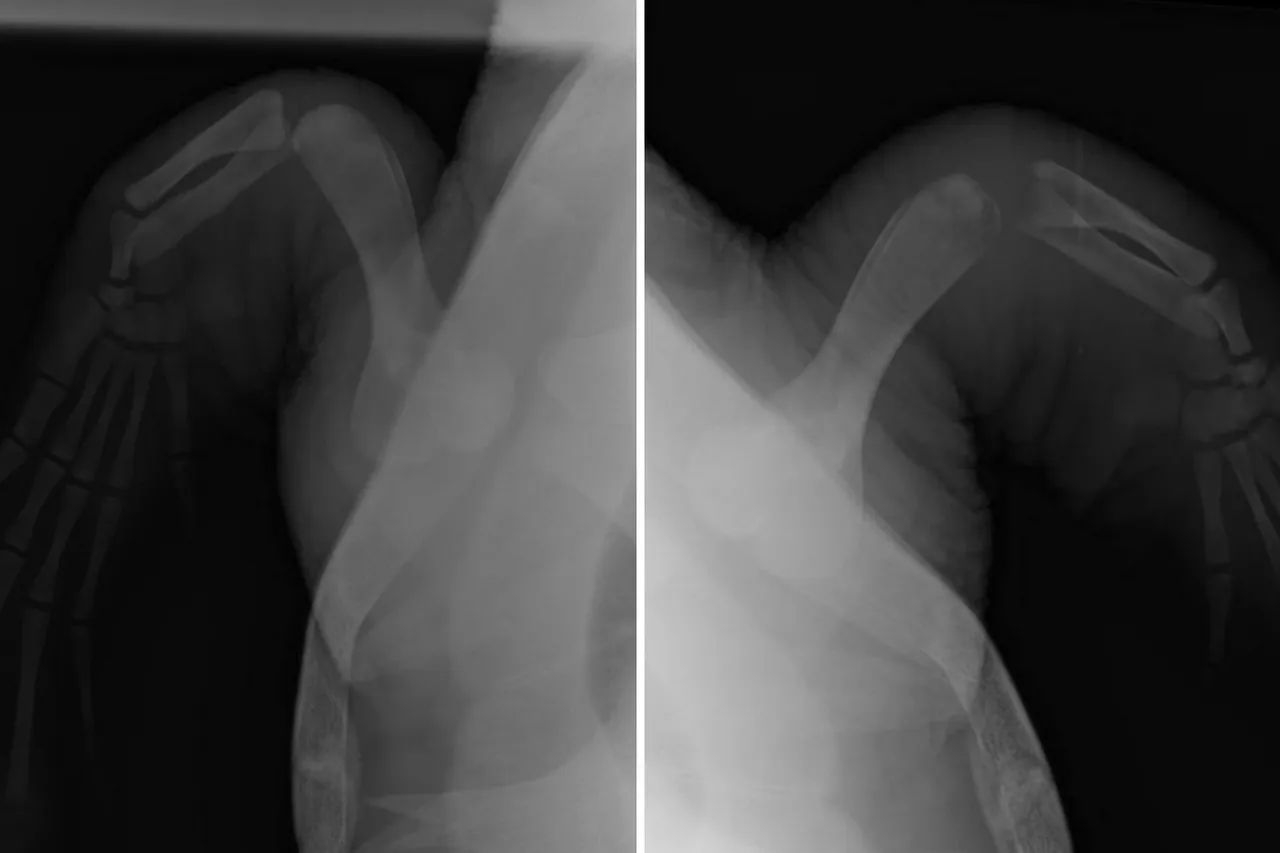

X-rays and joint samples were taken, revealing that Nobomvu has osteomyelitis, an infection of the bone, in her right flipper. Osteolytic (bone-eating) lesions in sea turtles have been identified as a secondary effect of traumatic injuries and compromised immune systems, and we know that the stress of being stranded, as well as the injuries associated with entanglement, can and do leave sea turtles immunocompromised. Due to the slow metabolisms of sea turtles, secondary infections like this only become evident much later than we would expect in mammals.